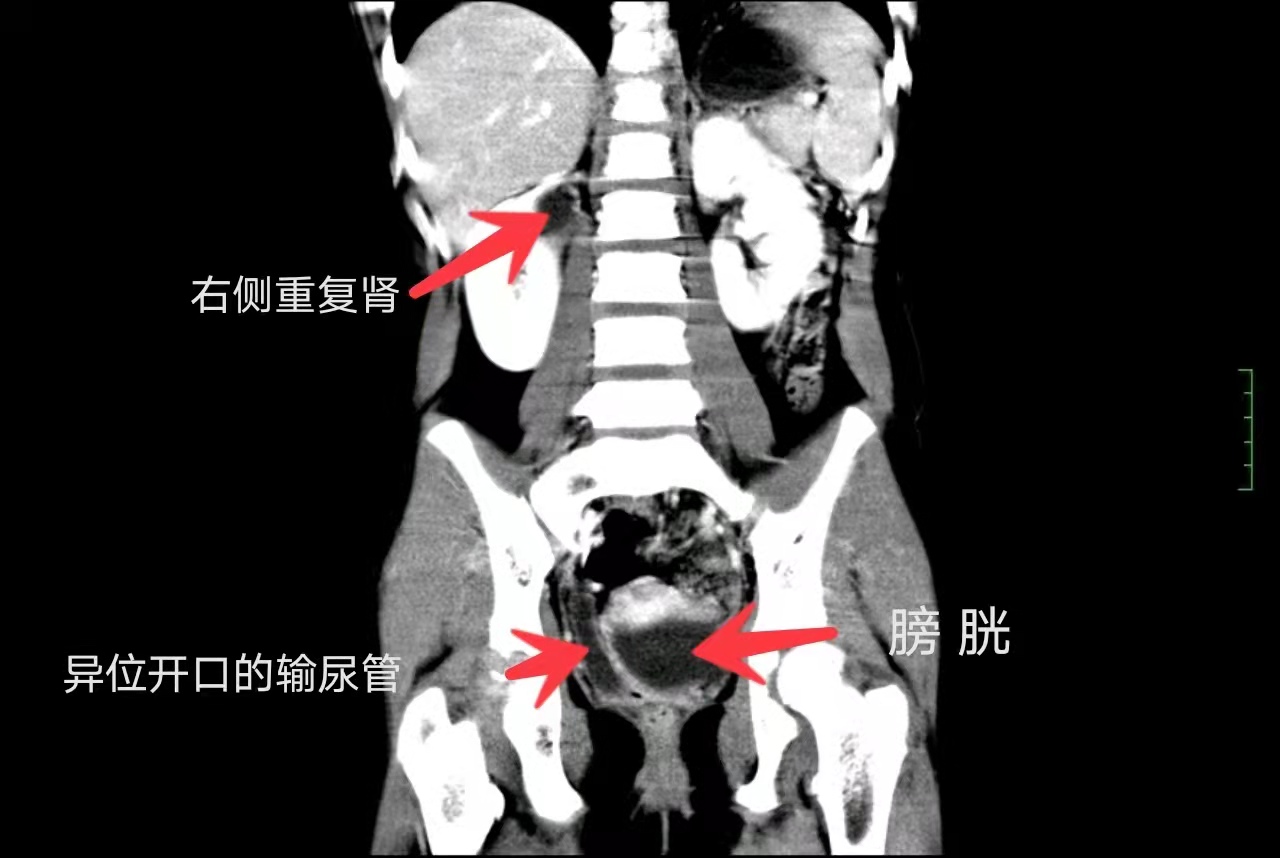

CT提示右侧重复肾输尿管畸形

入院完善相关检查后发现,患儿右侧双肾盂双输尿管重复畸形,输尿管异位开口于阴道右侧壁,原本只有棉签粗的输尿管也因此被撑成10倍大。导致茜茜长期漏尿的“真凶”找到了,就是这根“走错路”的输尿管。简单来说,茜茜3根输尿管中的一根由于远端没有按常理开口在膀胱上,而是“跑偏”绕过了膀胱这个“存水缸”,避开了尿道“阀门”的管控,导致“水龙头”关不住,才出现了漏尿。